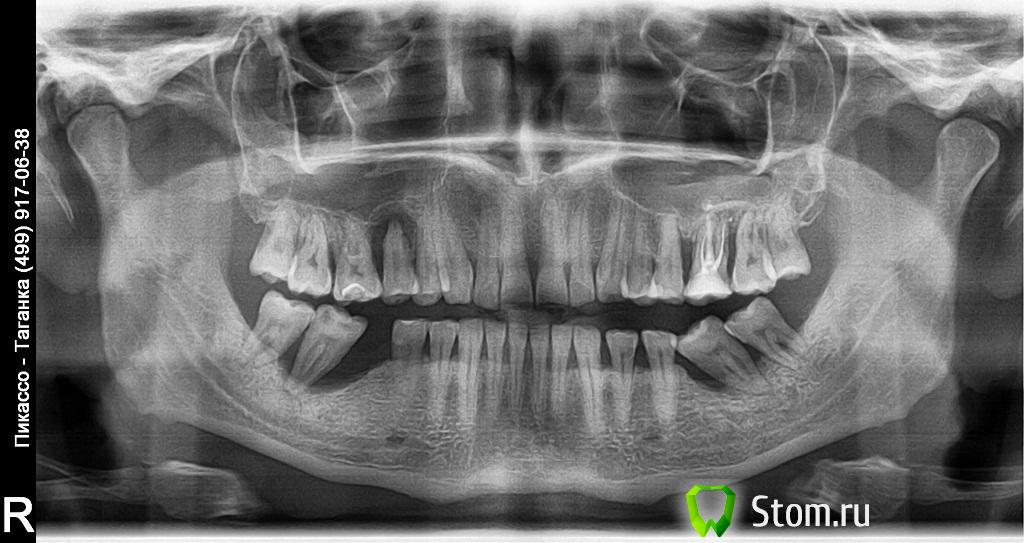

valiko76 Опубликовано 29 января, 2012 Поделиться Опубликовано 29 января, 2012 Всем добрый день!Вот и до меня докатилась эта болезнь нежданно-негаданно Начали шататься пару зубов и опухать десна вокруг них. Пошел в ближайшую к дому зубную клинику, вердикт - удалять 6 зубов!!!, лечить парадонтит, а потом протезы (мне 35 лет).Хочу попросить Вашего совета по карте лечения, может все не так плохо все-таки?Выкладываю снимок и вот карта лечения, которое мне назначили:1. Удаление 6 зубов - 47,48,37,38,27,152. Эндодонтическое лечение лечение зубов 25,28,16,143. Пародонтологическая чистка, кюретаж зубодесневых карманов 17,16,14; 25,264. Ортодонтическое лечение (говорят, что надо ставить брекеты для исправления прикуса, т.к. имеет место опускание верхней челюсти на нижнюю из-за чего и начался этот самый пародонтит).5. Ортопедическое лечение - предложили съемные протезы поставить (снизу протез, а сверху две коронки).Я спросил по поводу имплантов, сказали, что потом, когда кость восстановится об этом можно будет говорить, а пока коронки и протез.В связи с чем у меня вопросы - действительно ли все указанные зубы подлежат удалению? Правильно ли назначили лечение? Действительно нельзя сразу ставить импланты? И к какому бюджету вообще готовится при данном диагнозе? Ссылка на комментарий

ger_berra Опубликовано 30 января, 2012 Поделиться Опубликовано 30 января, 2012 (изменено) 1. 26 тоже2.Вероятно,для мостов .Не соглашайтесь,лучше импланты.Всё равно к этому придёте.3.Маловато...Нужно комплексное пародонтологическое лечение.4.Патология прикуса,конечно,играет большую роль в развитии пародонтита.Но у Вас добавляется ещё и вторичная деформация прикуса,обусловленная удалением 6-х зубов.Увеличилась перегрузка оставшихся жевательных зубов.Прикус стал "ещё более глубоким".5.Кость Ваша самостоятельно не восстановится.Надо делать пластику,потом имплантация.Съёмный протез как промежуточный вариант.Финансовая сторона вопроса обсуждается только с теми врачами,которые будут заниматься Вашей проблемой. Изменено 30 января, 2012 пользователем ger_berra Ссылка на комментарий